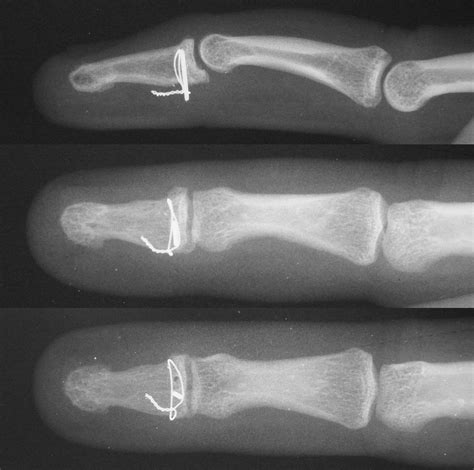

Surgery is typically reserved for complex, displaced, or intra-articular fractures. If the bone fragments are significantly separated or if the nail bed is severely damaged, an orthopedic surgeon may perform an internal fixation procedure using pins or screws to hold the bone in the correct anatomical position.